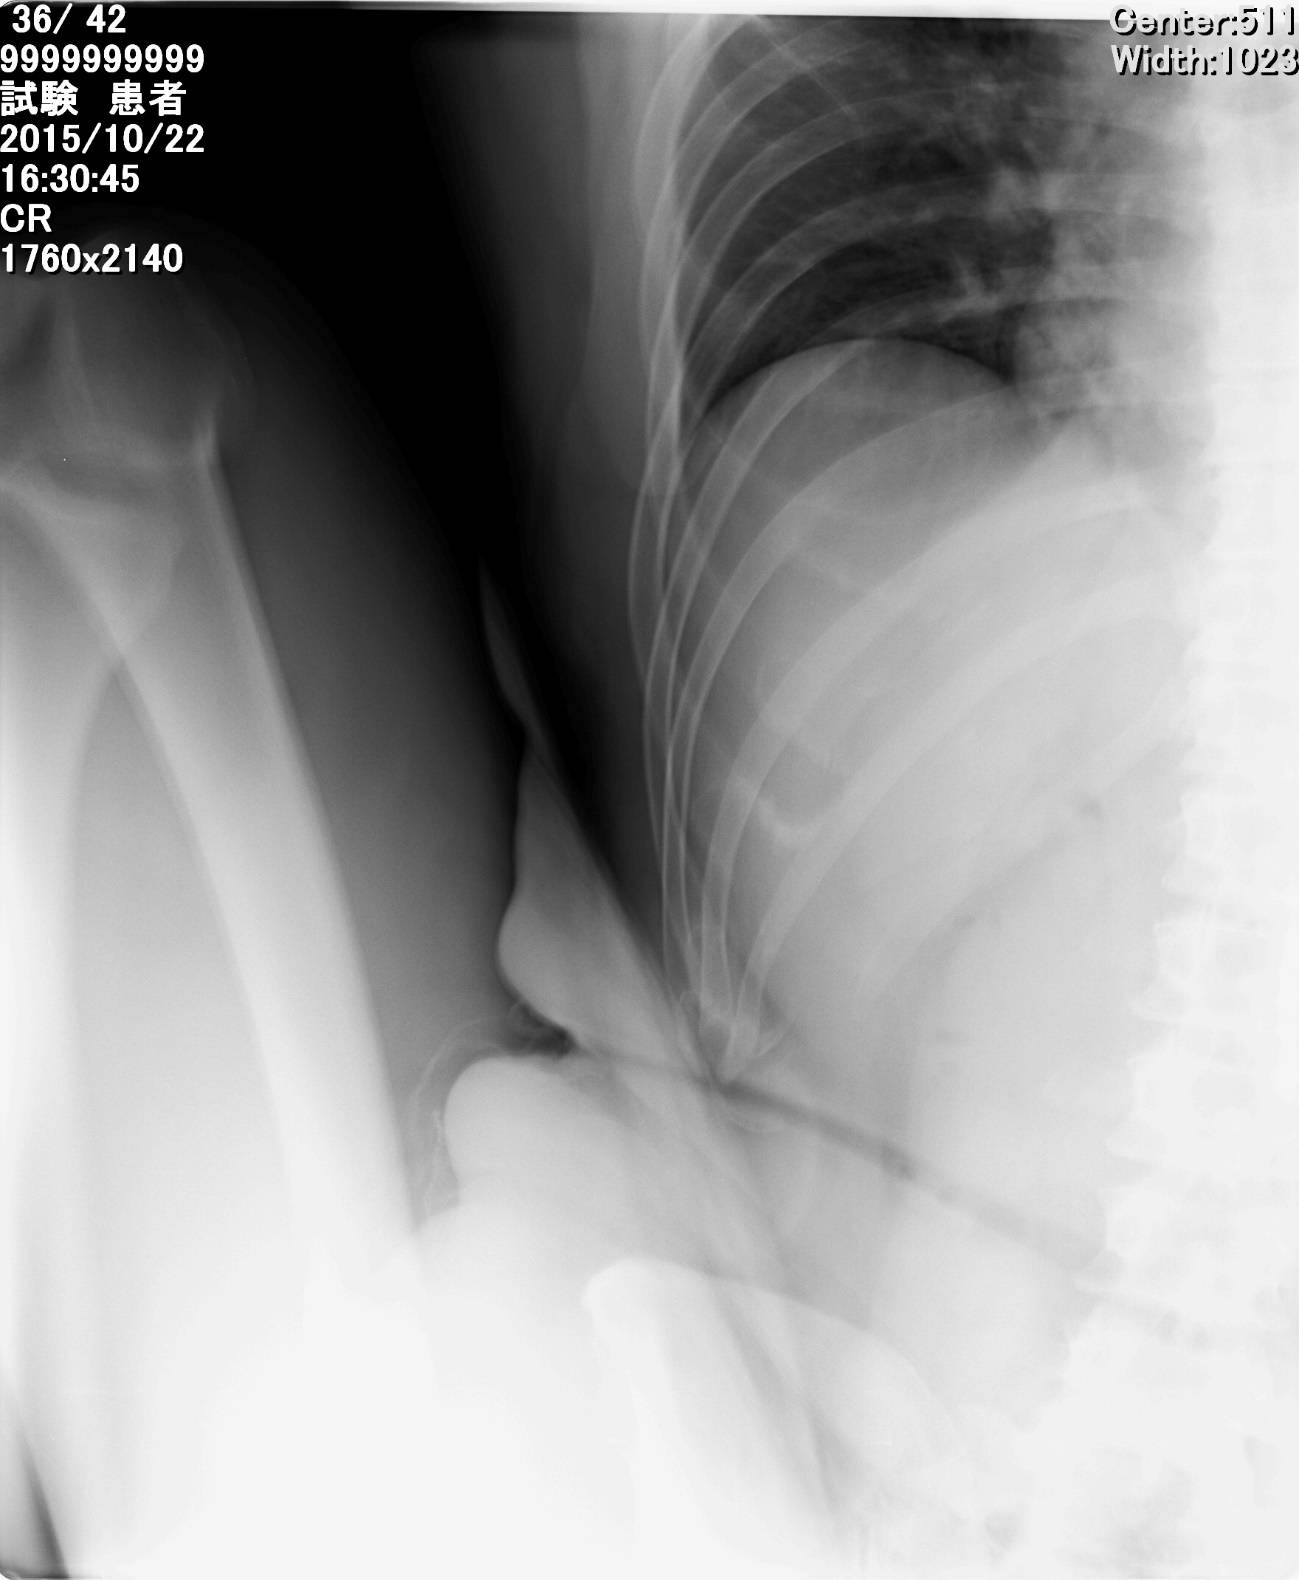

これについて私自身が被験者となり、レントゲンを撮って画像上で確認してみました。

こちらのレントゲンは、膝を身体の真正面方向に向かって動かしたときの最高点を撮影した画像です。膝のいちばん上は11番目の胸椎と12番目の胸椎の間くらいの高さでした。

次に真正面ではなく、膝を外側方向に向けて動かした場合、膝の最高点は7番目の胸椎の高さまで到達しました。

このように胸椎にして4つ分の高さに差が出たのです。(あくまでひとりのケースでの結果です)